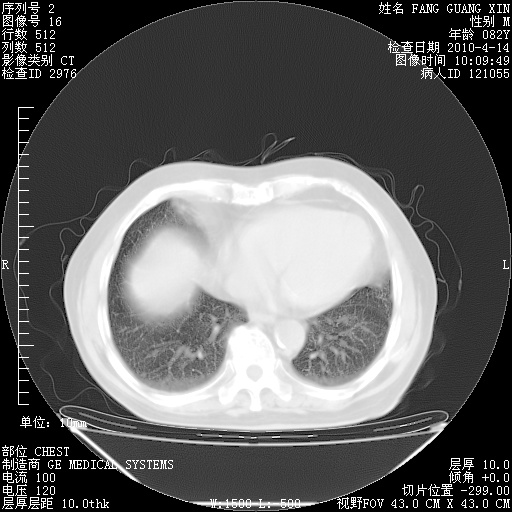

4月28日肺部CT——再次出现类似去年5月9日——透光度降低,“间质性”改变。

1221483 6 .bmp

1221483 7 .bmp

1221483 8 .bmp

1221483 9 .bmp